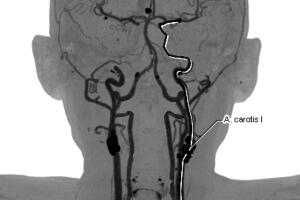

La presión arterial es la fuerza de la sangre contra las paredes de los vasos sanguíneos y se mide en milímetros de mercurio (mm Hg), explica la American Heart Association.

Se expresa en dos cifras, la primera llamada presión sistólica es aquella que hay cuando late el corazón, y la segunda o más pequeña, llamada presión diastólica, cuando el corazón descansa entre latidos.